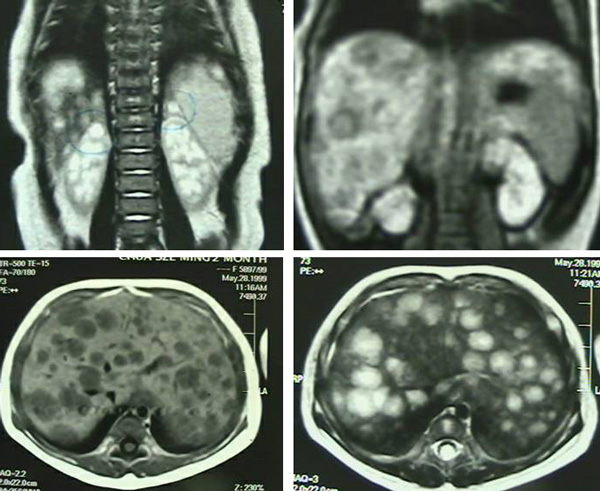

3 May 2011: A well-defined, lobulated mas – 5.0 x 7.6 x 4.8 cm in the left retroperitoneal / paraventerbral lumbar region, likely a neuroblastoma. There is no extension into the spinal canal.

5 May 2011: Image-guided biopsies – ganglioneuroblastoma, intermixed. Bone marrow, trephine biopsies – no metastatic neuroblastic tumour.

9 May 2011:

1. Soft tissue – primary tumour – intermixed ganglioneuroblatoma

2. Lymph node metastasis – poorly differentiated neuroblastoma

3. Tumour extending focally to resection margins

4. 7 out of 15 lymph nodes positive for metastatic tumour